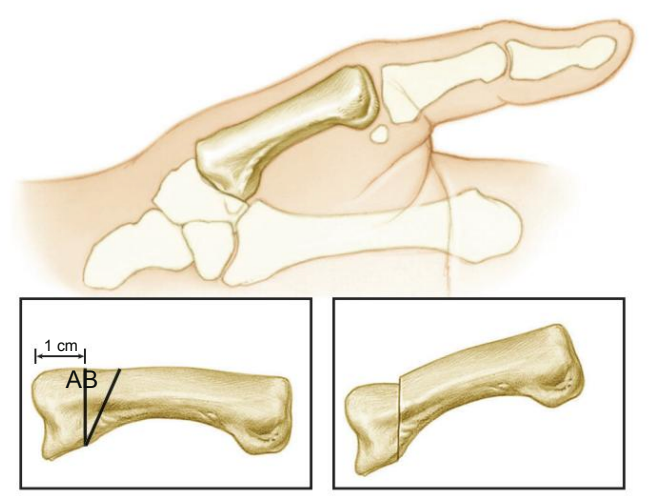

Nos casos mais avançados, o polegar pode começar a deformar. A base tende a colapsar em adução, enquanto a articulação mais distal compensa com hiperextensão, formando um padrão típico da doença .

Nos estágios iniciais, procedimentos como osteotomia do primeiro metacarpo ou reconstrução ligamentar podem ser indicados, com o objetivo de melhorar a mecânica da articulação e reduzir a dor .

Nos casos mais avançados, a cirurgia mais realizada é a retirada do trapézio (trapeziectomia), associada ou não à reconstrução ligamentar. Técnicas como a de Burton e Pellegrini utilizam tendões para estabilizar o polegar após a ressecção óssea.